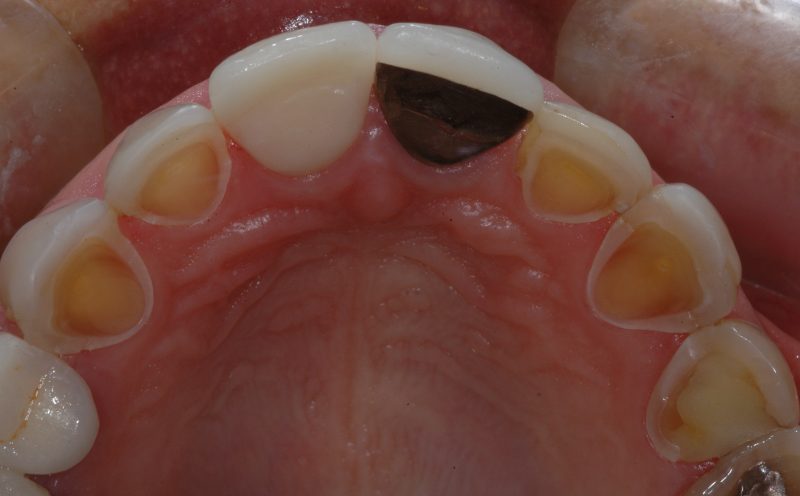

Self-induced vomiting increases the risk of dental erosion by a factor of 5.5 compared to healthy controls. These intrinsic erosion lesions are most commonly found on the palatal surfaces of the maxillary teeth, followed by the occlusal and then the buccal surfaces (Figs. 1–5).

While dental erosion in bulimic patients is most likely associated with oral retention of regurgitated gastric contents, dietary habits of bulimic patients may also include bingeing on high-energy foods and foods with high erosive potential, which may further exacerbate erosion.